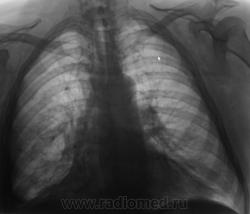

Пол пациента: Мужской пол Тип патологии: Другое Область исследования: Грудная клетка и верхние дыхательные пути Методы исследования: Rg При расшифровке фицровых флюорограмм пациент взят на контроль. Жалоб нет. Пациент преклонного возраста. Ваше мнение коллеги? https://radiomed.ru/sites/default/files/styles/case_slider_image/public/2.U.Kontrol.JPG?itok=D_X_PWlr https://radiomed.ru/sites/default/files/styles/case_slider_image/public/3.U.Kontrol.JPG?itok=WUYf75C2 https://radiomed.ru/sites/default/files/styles/case_slider_image/public/4.U.Kontrol.JPG?itok=Qim3Ihlu ID:29 Чт, 07/01/2010 - 15:39 #1 Анатолий Владим... Не на сайте Был на сайте: 8 лет 3 месяцев назад Зарегистрирован: 16.10.2009 - 21:16 Публикации: 1941 Похоже на ателектаз десятого сегмента справа. Ср, 13/01/2010 - 20:55 #2 Ольга Дмитриевна Не на сайте Был на сайте: 16 лет 2 месяцев назад Зарегистрирован: 13.01.2010 - 16:55 Публикации: 168 Средней доли тоже нет. Центральный рак? КТ бы надо. Красота - гормон карьерного роста! Ср, 10/08/2011 - 19:38 #3 Nikolas Не на сайте Был на сайте: 1 месяц 3 недели назад Зарегистрирован: 21.12.2010 - 20:37 Публикации: 4560 Уважаемый Валентин Львович! Что же у больного все-таки оказалось после дообследования? С уважением Nikolas Пт, 12/08/2011 - 22:11 #4 Катенёв Валенти... Не на сайте Был на сайте: 7 лет 5 месяцев назад Зарегистрирован: 22.03.2008 - 22:15 Публикации: 54876 Пациентку пролечили в течение 2-х недель в Т.О., сделали "контроль", написали возрастную норму.

Похоже на ателектаз десятого сегмента справа.

Средней доли тоже нет. Центральный рак? КТ бы надо.

Пациентку пролечили в течение 2-х недель в Т.О., сделали "контроль", написали возрастную норму.